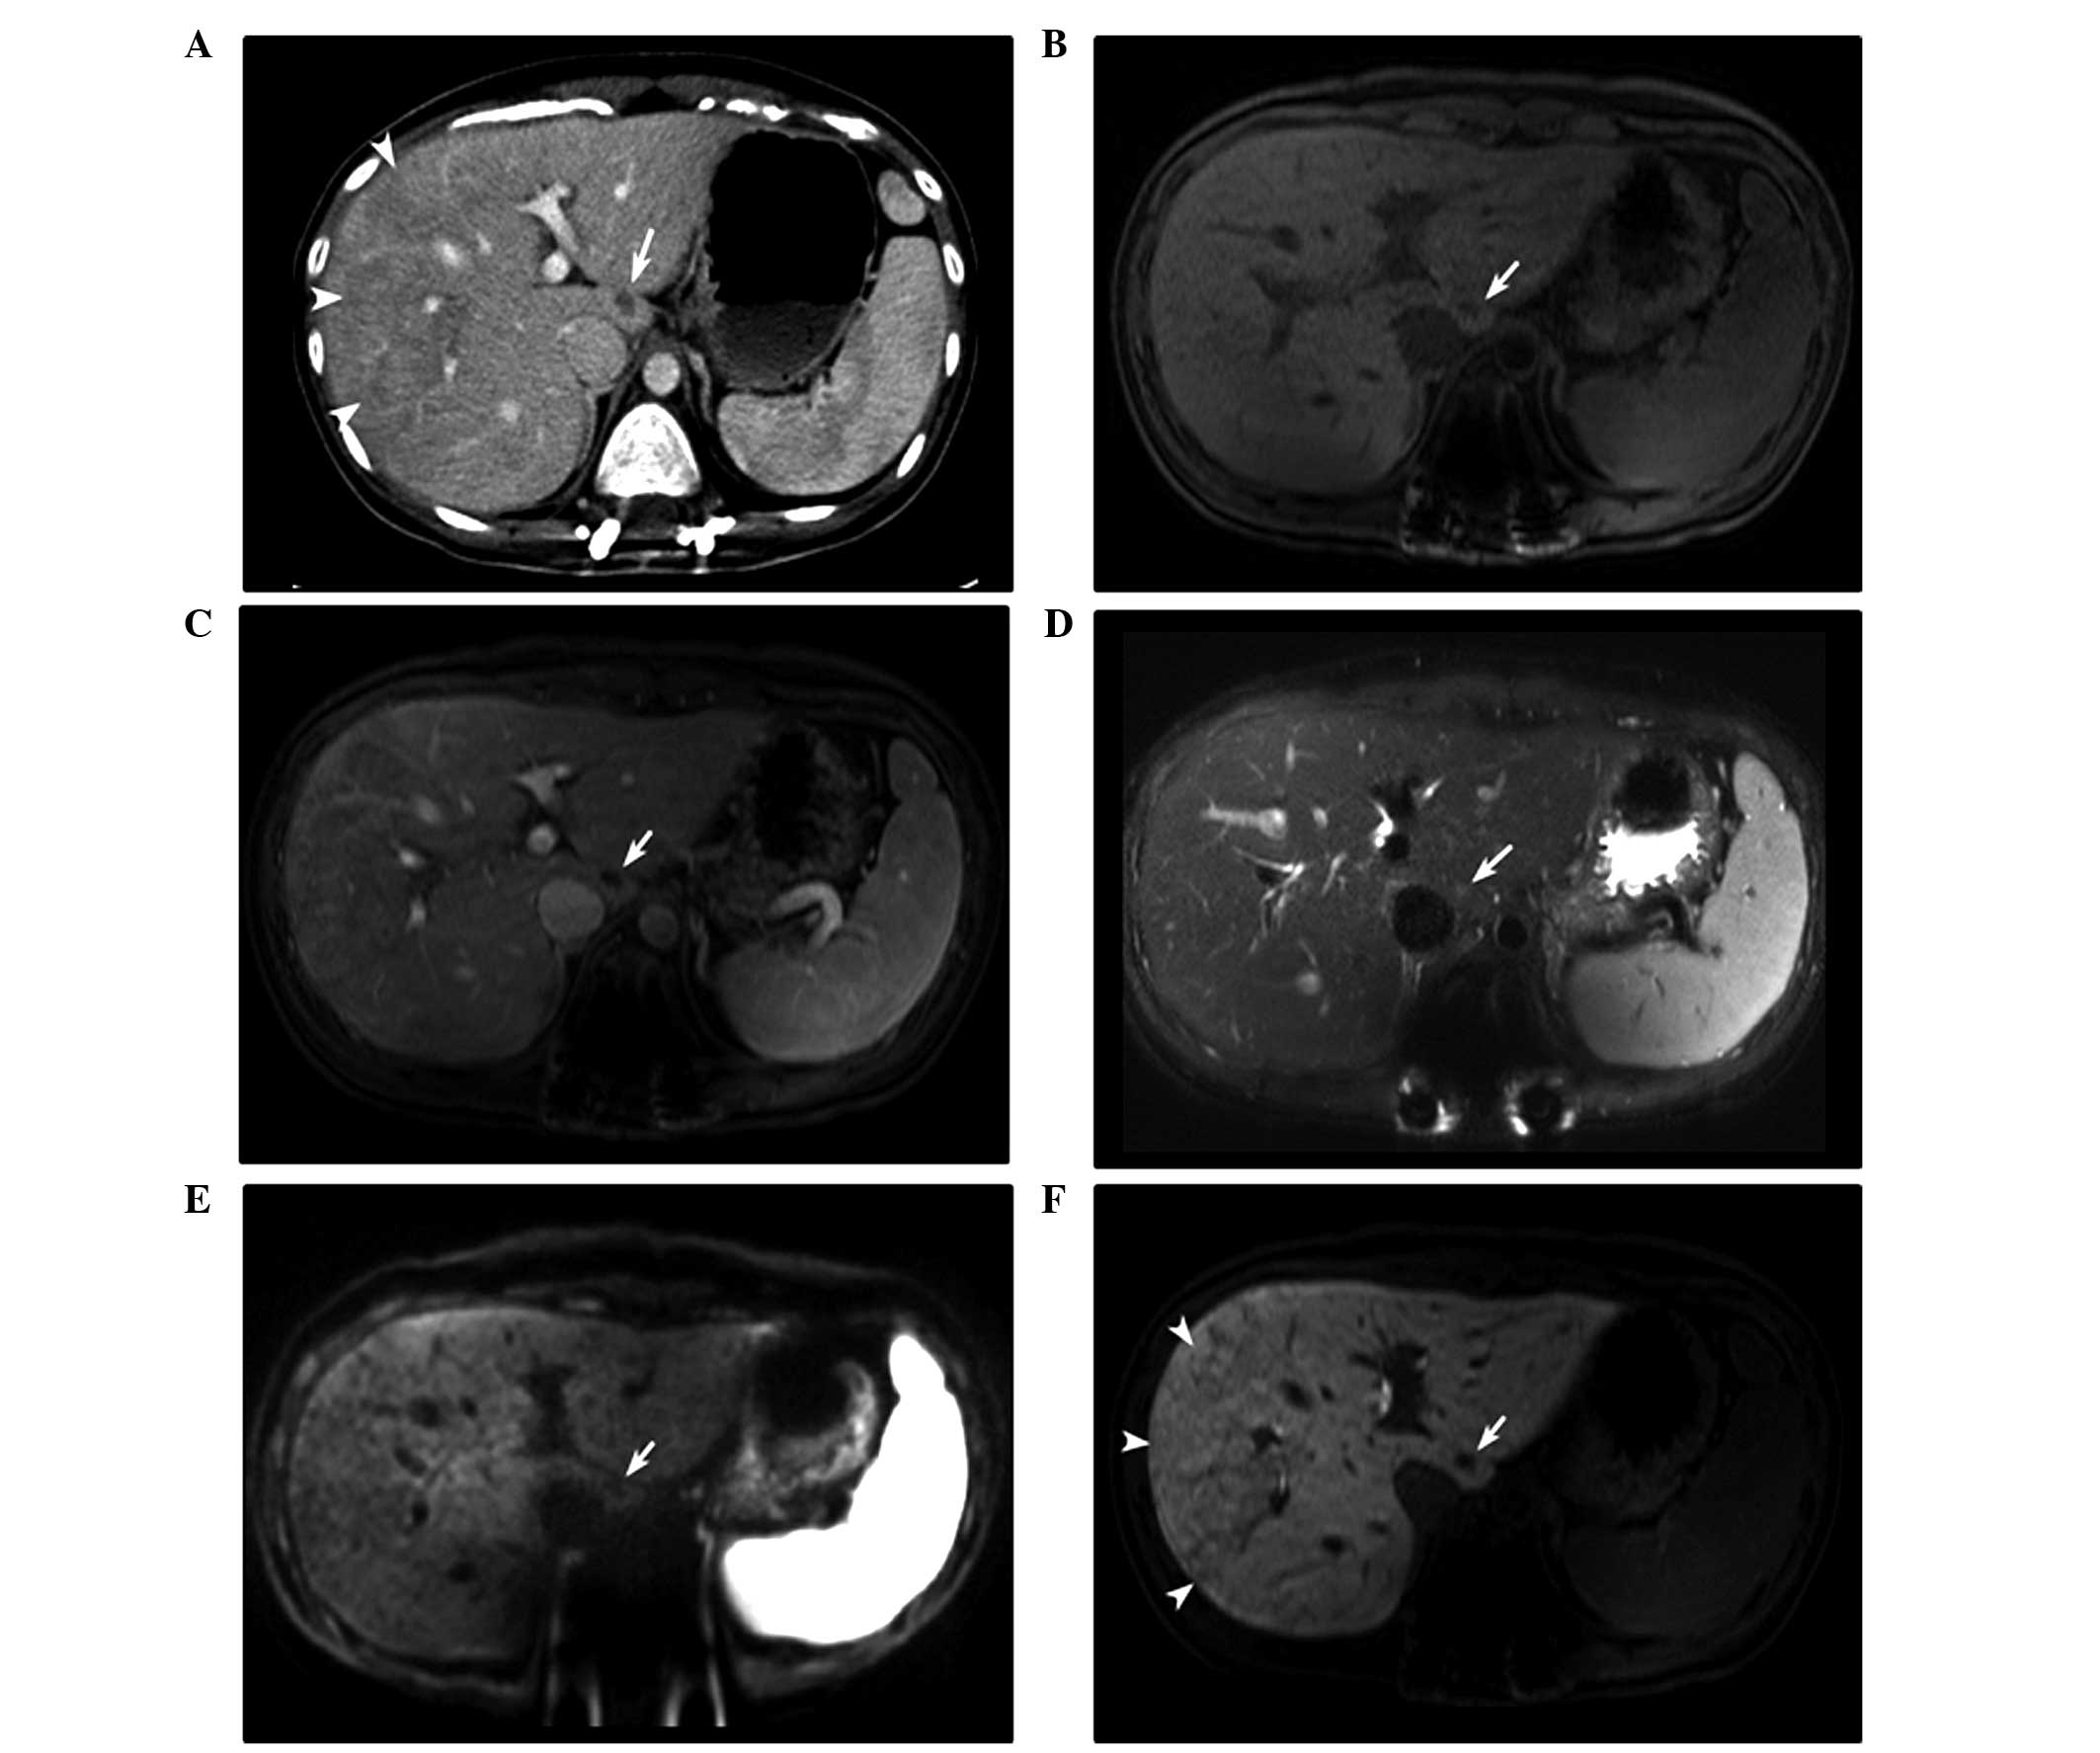

The contrast-enhanced abdominal computed tomography (CT) scan revealed a novel tiny, nodular, low-density lesion in segment 1 of the liver. EOB-MRI identified that the lesion was 1 cm in size at the widest point, ovoid and hypointense on the pre-contrast and portal-phase T1-weighted imaging, without enhancement. EOB-MRI revealed partial hyperintensity on the T2-weighted imaging and a hypointense nodule on diffusion-weighted imaging (Fig. 1). Positron emission tomography (PET)-CT identified no clear abnormal fluorodeoxyglucose (FDG) uptake suggestive of malignancy. Although the findings did not exclude a metastatic lesion, adjuvant chemotherapy [oxaliplatin (190 mg, day 1) and capecitabine (1,500 mg, twice daily, days 1–14) every 3 weeks] was administered, with a follow-up abdominal CT performed one month later.

Figure 1.

Imaging studies of a 22-year-old woman with a single, newly developed, 1.0 cm lesion in segment 1 of the liver, detected 3 months subsequent to the initiation of oxaliplatin-based adjuvant chemotherapy for colon cancer. (A) Transverse contrast-enhanced computed tomography images revealed a nodular low-density lesion (arrow) and poorly enhanced areas (arrowheads). On the EOB-MRI images, the lesion (arrows) was hypointense in the (B) pre-contrast and (C) portal phase T1-weighted images without enhancement, (D) partially hyperintense on the T2-weighted images, and (E) hypointense on the diffusion-weighted images (b = 800 sec/mm2). (F) EOB-MRI images revealed reticular hypointensity on the hepatobiliary phase images in the right lobe of the liver (arrowheads). EOB-MRI, gadoxetic acid-enhanced magnetic resonance imaging.

Although oxaliplatin-induced SOS is usually asymptomatic, it may be associated with an increased perioperative morbidity and bleeding risk (9). Therefore, there have been several studies that investigated the predictive parameters for oxaliplatin-induced SOS, such as EOB-MRI findings, the volume of the spleen, the levels of hyaluronic acid, the indocyanine green retention rate at 15 min (ICG-R15), and aspartate aminotransferase (AST) level (8,9,12). Shin et al (4) reported that reticular hypointensity on hepatobiliary phase images of EOB-MRI was highly specific for SOS. Shin et al divided the presence of reticular hypointensity into 5 levels, and levels 4 and 5 were considered to indicate SOS (4). In the present study, transverse contrast-enhanced CT imaging revealed diffuse, poorly enhanced regions on the right lobe of the liver, and EOB-MRI revealed confidence level 4 reticular hypointensity on the hepatobiliary phase images in the same region (Fig. 1F). In addition, the AST levels (54 IU/l) and ICG-R15 (12.25%) were increased prior to surgery. The findings suggested a diagnosis of oxaliplatin-induced SOS in the background liver. However, during the initial evaluation, only the focal lesion in segment 1 was focused on, making the diagnosis of SOS prior to surgery extremely challenging.